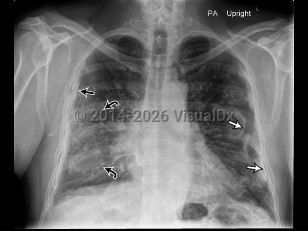

Asbestosis is a fibrotic lung disease resulting from extensive inhalation of asbestos fibers. Symptoms include insidious onset of cough, dyspnea, and chest discomfort. Pleural effusions and mesothelioma are associated disorders. Latency between exposure to asbestos and development of disease is typically at least 20 years, making diagnosis difficult.

Asbestosis